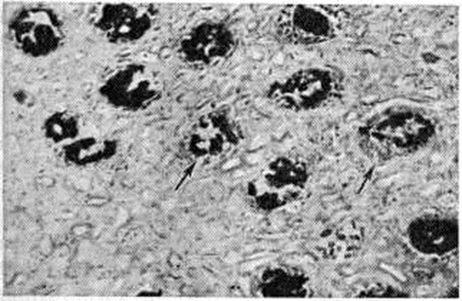

Тромбоз капилляров клубочков как проявление диссеминированного внутрисосудистого свёртывания крови наблюдается чаще при бактериемическом шоке и патологически протекающей беременности. К проявлениям диссеминированного внутрисосудистого свёртывания крови с развитием генерализованного феномена Швартцмана— Санарелли (смотри полный свод знаний: Швартцмана феномен) относят также симметричный кортикальный некроз почек (смотри полный свод знаний: Геморрагический кортикальный некроз почек). Различают тотальную, субтотальную, сегментарную и малую формы некроза. При тотальной форме сохраняются почечные пирамиды; при субтотальной — в корковом веществе встречаются островки непоражённой ткани; при сегментарной — очаги некроза имеют вид инфарктов, окружённых геморрагиями; малые формы удаётся выявить только при микроскопическом исследовании. При затянувшейся острой Почечная недостаточность некротизованное корковое вещество почки истончается. Отравление этиленгликолем влечёт за собой симметричный кортикальный некроз почек, сочетающийся с гликолевым нефрозом, а при патологии беременности — с острой гемоглобинурией, апоплексией и некрозом коркового вещества надпочечников, некрозом передней доли гипофиза. Гистологически отмечается коагуляционный некроз коркового вещества почки. В клубочковых кровеносных капиллярах и артериолах обнаруживают фибриновые тромбы (рисунок 2, а). Зона некроза ограничена демаркационным валом из полиморфно-ядерных лейкоцитов. Аргирофильный каркас разрушен. В дальнейшем некротизированные участки подвергаются организации, фиброзу и кальцинозу.

Рис. 2.

Микропрепараты почки при острой почечной недостаточности (отравление этиленгликолем): а — в клубочковых кровеносных капиллярах видны пристеночные тромбы (указаны стрелками); окраска по Маллори; × 110; б — баллонная дистрофия эпителия канальцев; окраска гематоксилин-эозином; × 100.